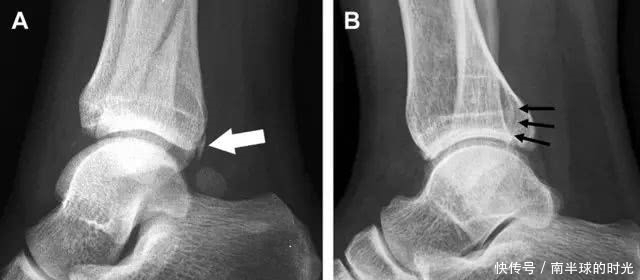

涉及到三角韧带和外侧副韧带(LCL)的复杂性骨折常常不难发现,尤其是存在表面软组织肿胀时。然而,后胫腓韧带牵拉引起的胫骨后踝骨折则很难发现。这些骨折大小不一(图 2),却很重要,因为他们常与胫骨远端螺旋骨折有关,或者是三踝骨折的一部分。

图 2 胫骨后踝骨折。A 侧位片示来源于胫骨后踝的一个小骨折碎片(箭头),因踝部扭伤导致;B 另一位跖屈损伤的患者,侧位片示一个大骨折块(箭头)